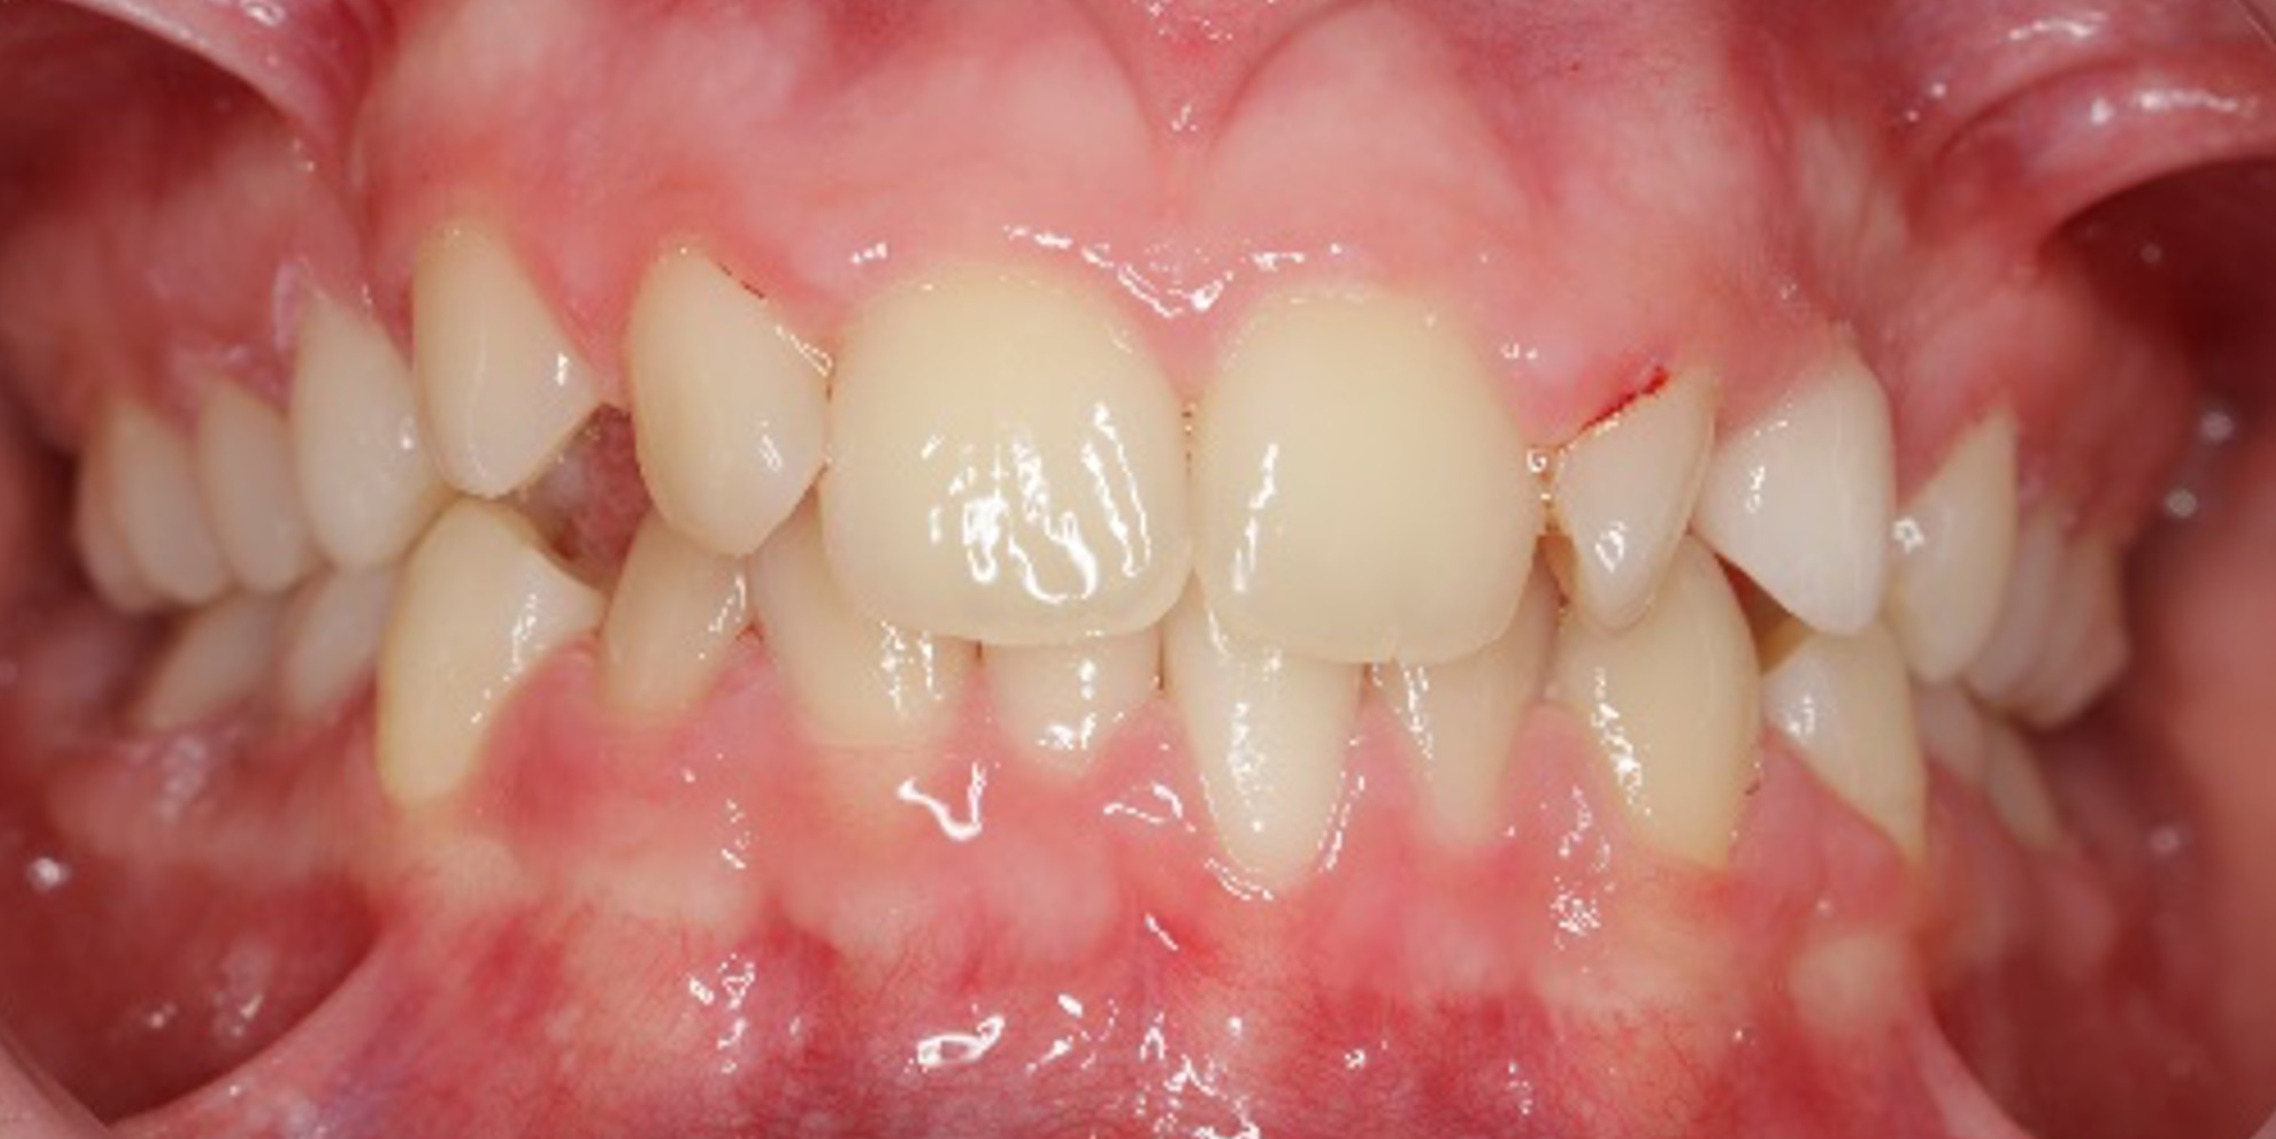

The 14-year-old female patient visited the orthodontic practice in February 2021. The chief complaint was that her upper arch was affecting her confidence in her smile. Upon examination, the patient was found to have a normodivergent facial pattern and a skeletal class II with mandibular retrusion. An intraoral examination revealed narrow arches, a class II molar and canine relationship, deep bite, retroclined upper and lower incisors, and retained teeth 63, 74, and 84.

After undergoing maxillary expansion, Dr. Sorina Blaj assessed the patient again in September 2021, and at that point, tooth 84 had exfoliated, tooth 44 had erupted, and tooth 23 had started to erupt.